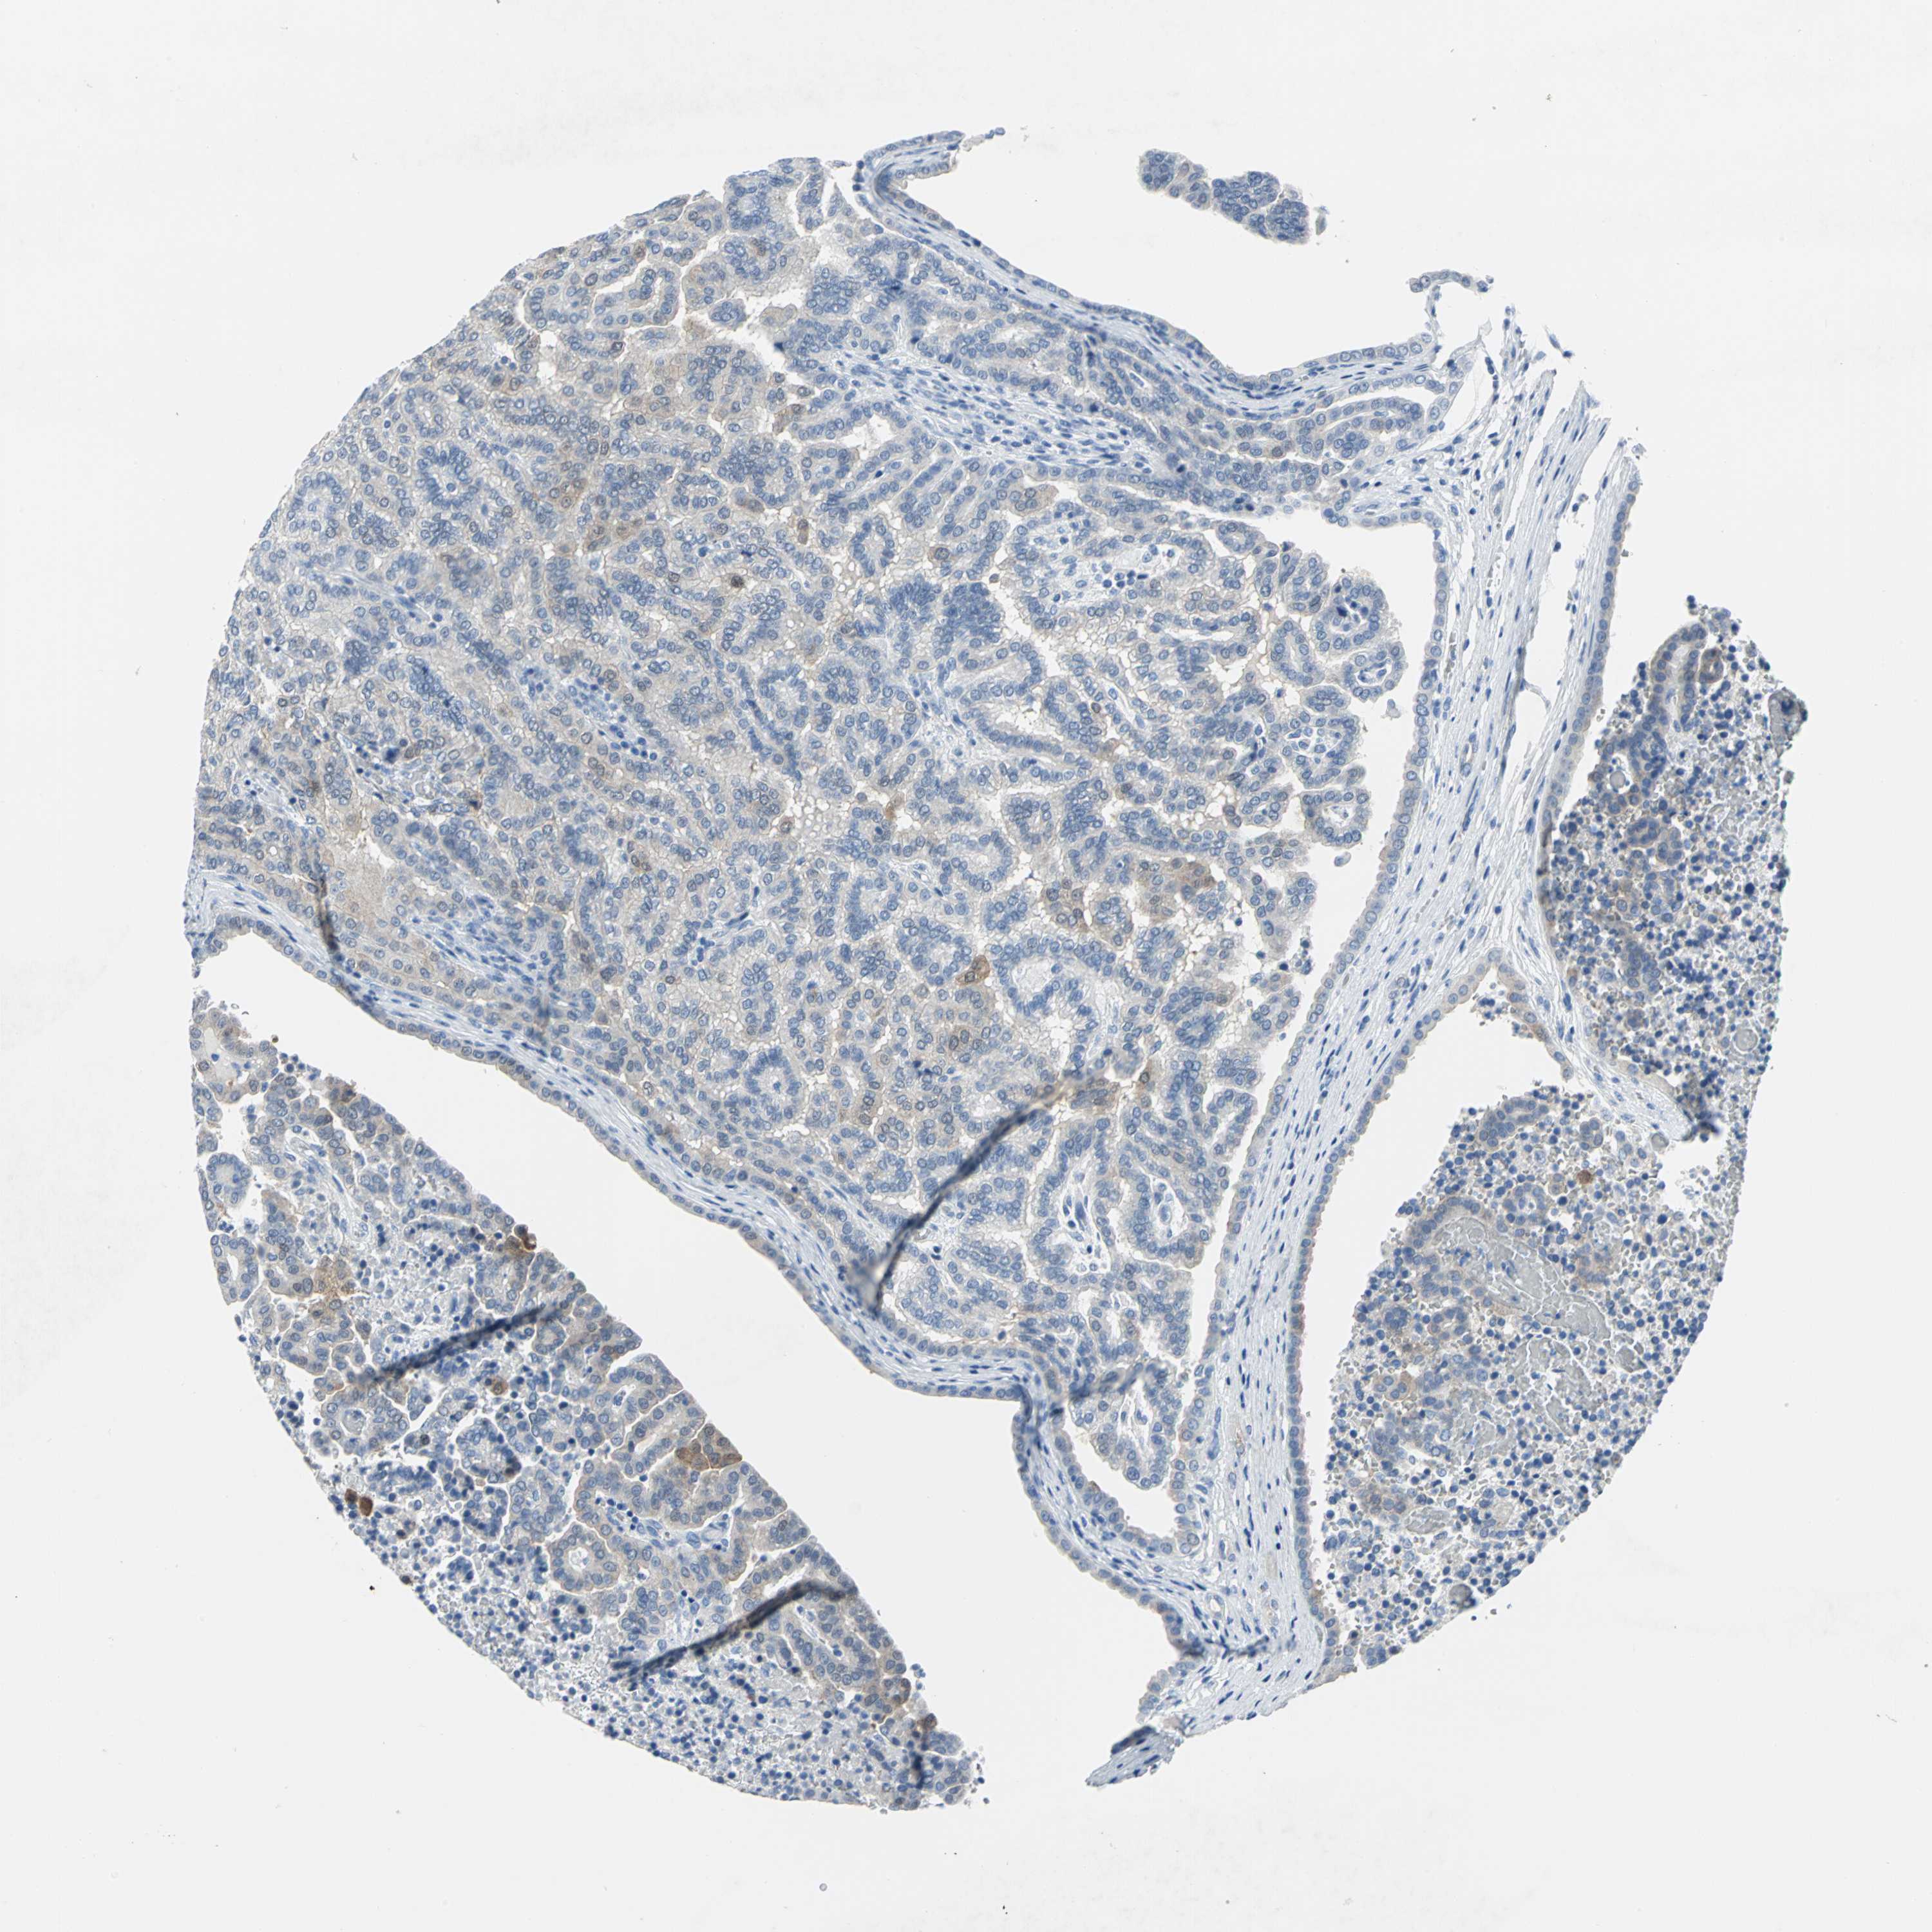

KIDNEY CHROMOPHOBE (TCGA) - Interactive survival scatter ploti

The Survival Scatter plot shows the clinical status (i.e. dead or alive) for all individuals in the patient cohort, based on the same data that underlies the corresponding Kaplan-Meier plots. Patients that are alive at last time for follow-up are shown in blue and patients who have died during the study are shown in red.

The x-axis shows the expression levels (FPKM) of the investigated gene in the tumor tissue at the time of diagnosis. The y-axis shows the follow-up time after diagnosis (years). Both axes are complimented with kernel density curves demonstrating the data density over the axes. The top density plot shows the expression levels (FPKM) distribution among dead (red) and alive patients (blue). The right density plot shows the data density of the survived years of dead patients with high and low expression levels respectively, stratified using the cutoff indicated by the vertical dashed line through the Survival Scatter plot. This cutoff is automatically defined based on the FPKM cutoff that minimizes the p-score. The cutoff can be changed by dragging the vertical line or by entering a cutoff value in the square labeled "Current cut-off".

Under the Survival Scatter plot the p-score landscape (black curve; left axis) is shown together with dead median separation (red curve; right axis). Dead median separation is the difference in median mRNA expression between patients who have died with high and low expression, respectively. It is calculated as follows: median FPKM expression of dead patients with high expression - median FPKM expression of dead patients with low expression. This is intended to aid the user in visually exploring custom cutoffs and the associated p-scores and dead median separation.

Individual patient data is displayed and can be filtered by clicking on one or more of the category buttons on the top of the page. Categories describing expression level and patient information include: high, low, alive, dead, female, male and tumor stages. The scale of the x-axis can be toggled between linear and log-scale by clicking on the "x log" button. Mouse-over function shows TCGA ID, patient information and mRNA expression (FPKM) for each patient.

& Survival analysisi

Kaplan-Meier plots summarize results from analysis of correlation between mRNA expression level and patient survival. Patients were divided based on level of expression into one of the two groups "low" (under cut off) or "high" (over cut off). X-axis shows time for survival (years) and y-axis shows the probability of survival, where 1.0 corresponds to 100 percent.

SFN is not prognostic in Kidney Chromophobe (TCGA)

Best expression cut offi

Based on the FPKM value of each gene, patients were classified into two groups and association between prognosis (survival) and gene expression (FPKM) was examined. The best expression cut-off refers the FPKM value that yields maximal difference with regard to survival between the two groups at the lowest log-rank P-value. Best expression cut-off was selected based on survival analysis .

When clicking on this number, the vertical dashed line indicating cut-off, the interactive survival plot, and the Kaplan-Meier curve will be adjusted to show results based on the best expression cut-off.

: 2.08

P scorei

Log-rank P value for Kaplan-Meier plot showing results from analysis of correlation between mRNA expression level and patient survival.

N/A

TCGA RNA samplesi

RNA-seq data is reported as average FPKM (number Fragments Per Kilobase of exon per Million reads), generated by the The Cancer Genome Atlas (TCGA) .

Normal distribution across the dataset is visualized with box plots, shown as median and 25th and 75th percentiles. Points are displayed as outliers if they are above or below 1.5 times the interquartile range. FPKM values of the individual samples are presented next to the box plot.

Average pTPM 3.5

Number of samples 64